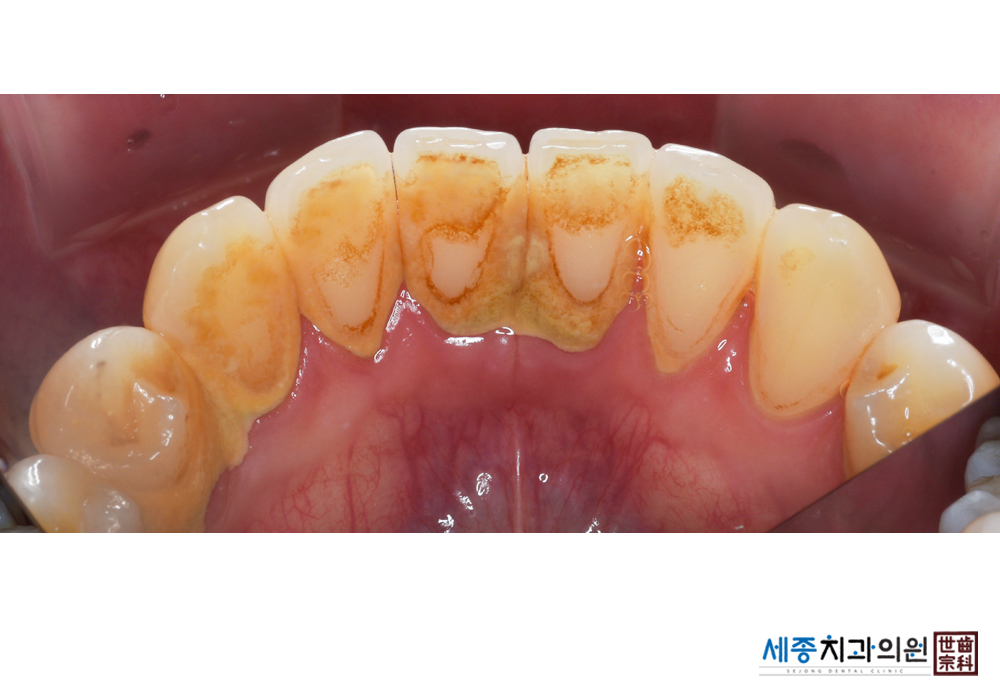

[스케일링] 치주질환 예방 스케일링 치료

치료후 : 2019-01-28

가글마취&저주파 스켈러를 사용한 스케일링